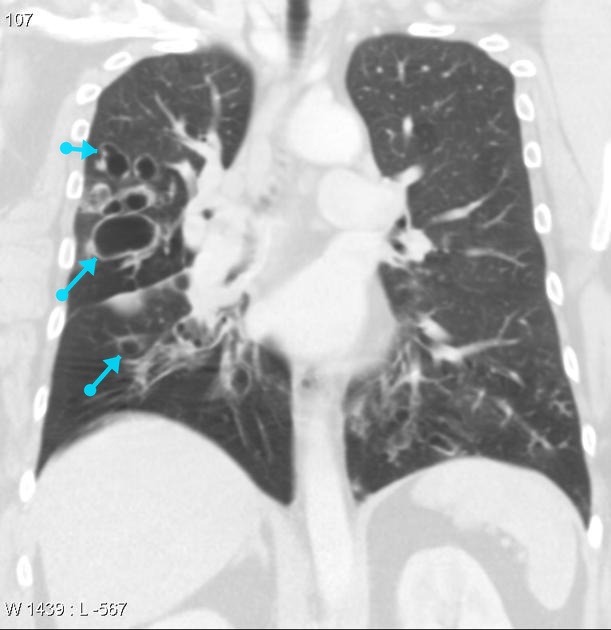

What's the Diagnosis?